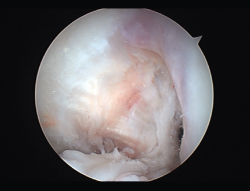

El tratamiento de un paciente que sufre una rotura aguda del LCA (Figura 2) sigue siendo motivo de discusión(9). Hay muchos condicionantes que influyen en el manejo terapéutico de estas lesiones (ya sea quirúrgico como no quirúrgico), como son la edad, la ocupación, la actividad deportiva, las lesiones asociadas, el grado de laxitud de la rodilla, las expectativas o las recidivas de la lesión, entre otras. El riesgo de artrosis tras la rotura aguda del LCA será mayor en ambos grupos con respecto a la población sana, sea cual sea el tratamiento(12). Los factores de riesgo más importantes para el desarrollo de artropatía son: lesión meniscal, meniscectomía e injerto hueso-tendón-hueso (HTH).

Figura 2. Rotura aguda del ligamento cruzado anterior.